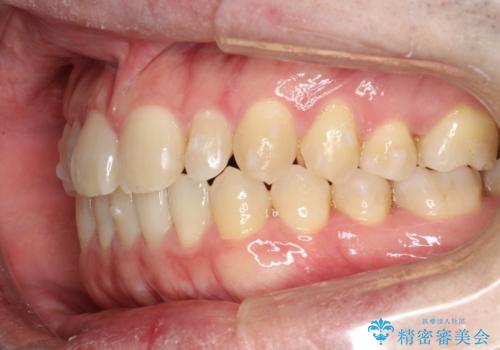

前歯の真ん中の隙間を閉じたい インビザラインによる目立たない矯正

- 上顎の正中の隙間が気になるとのことで来院されました。

下の歯と歯の間をわずかに削り、スペースを作り、正中の隙間を閉じる計画としました。

装置はインビザラインにて行いました。

インビザラインで目立たずに矯正治療を行うことができました。

使用時間を守っていただけたので、比較的スムーズに矯正を終了することができました。